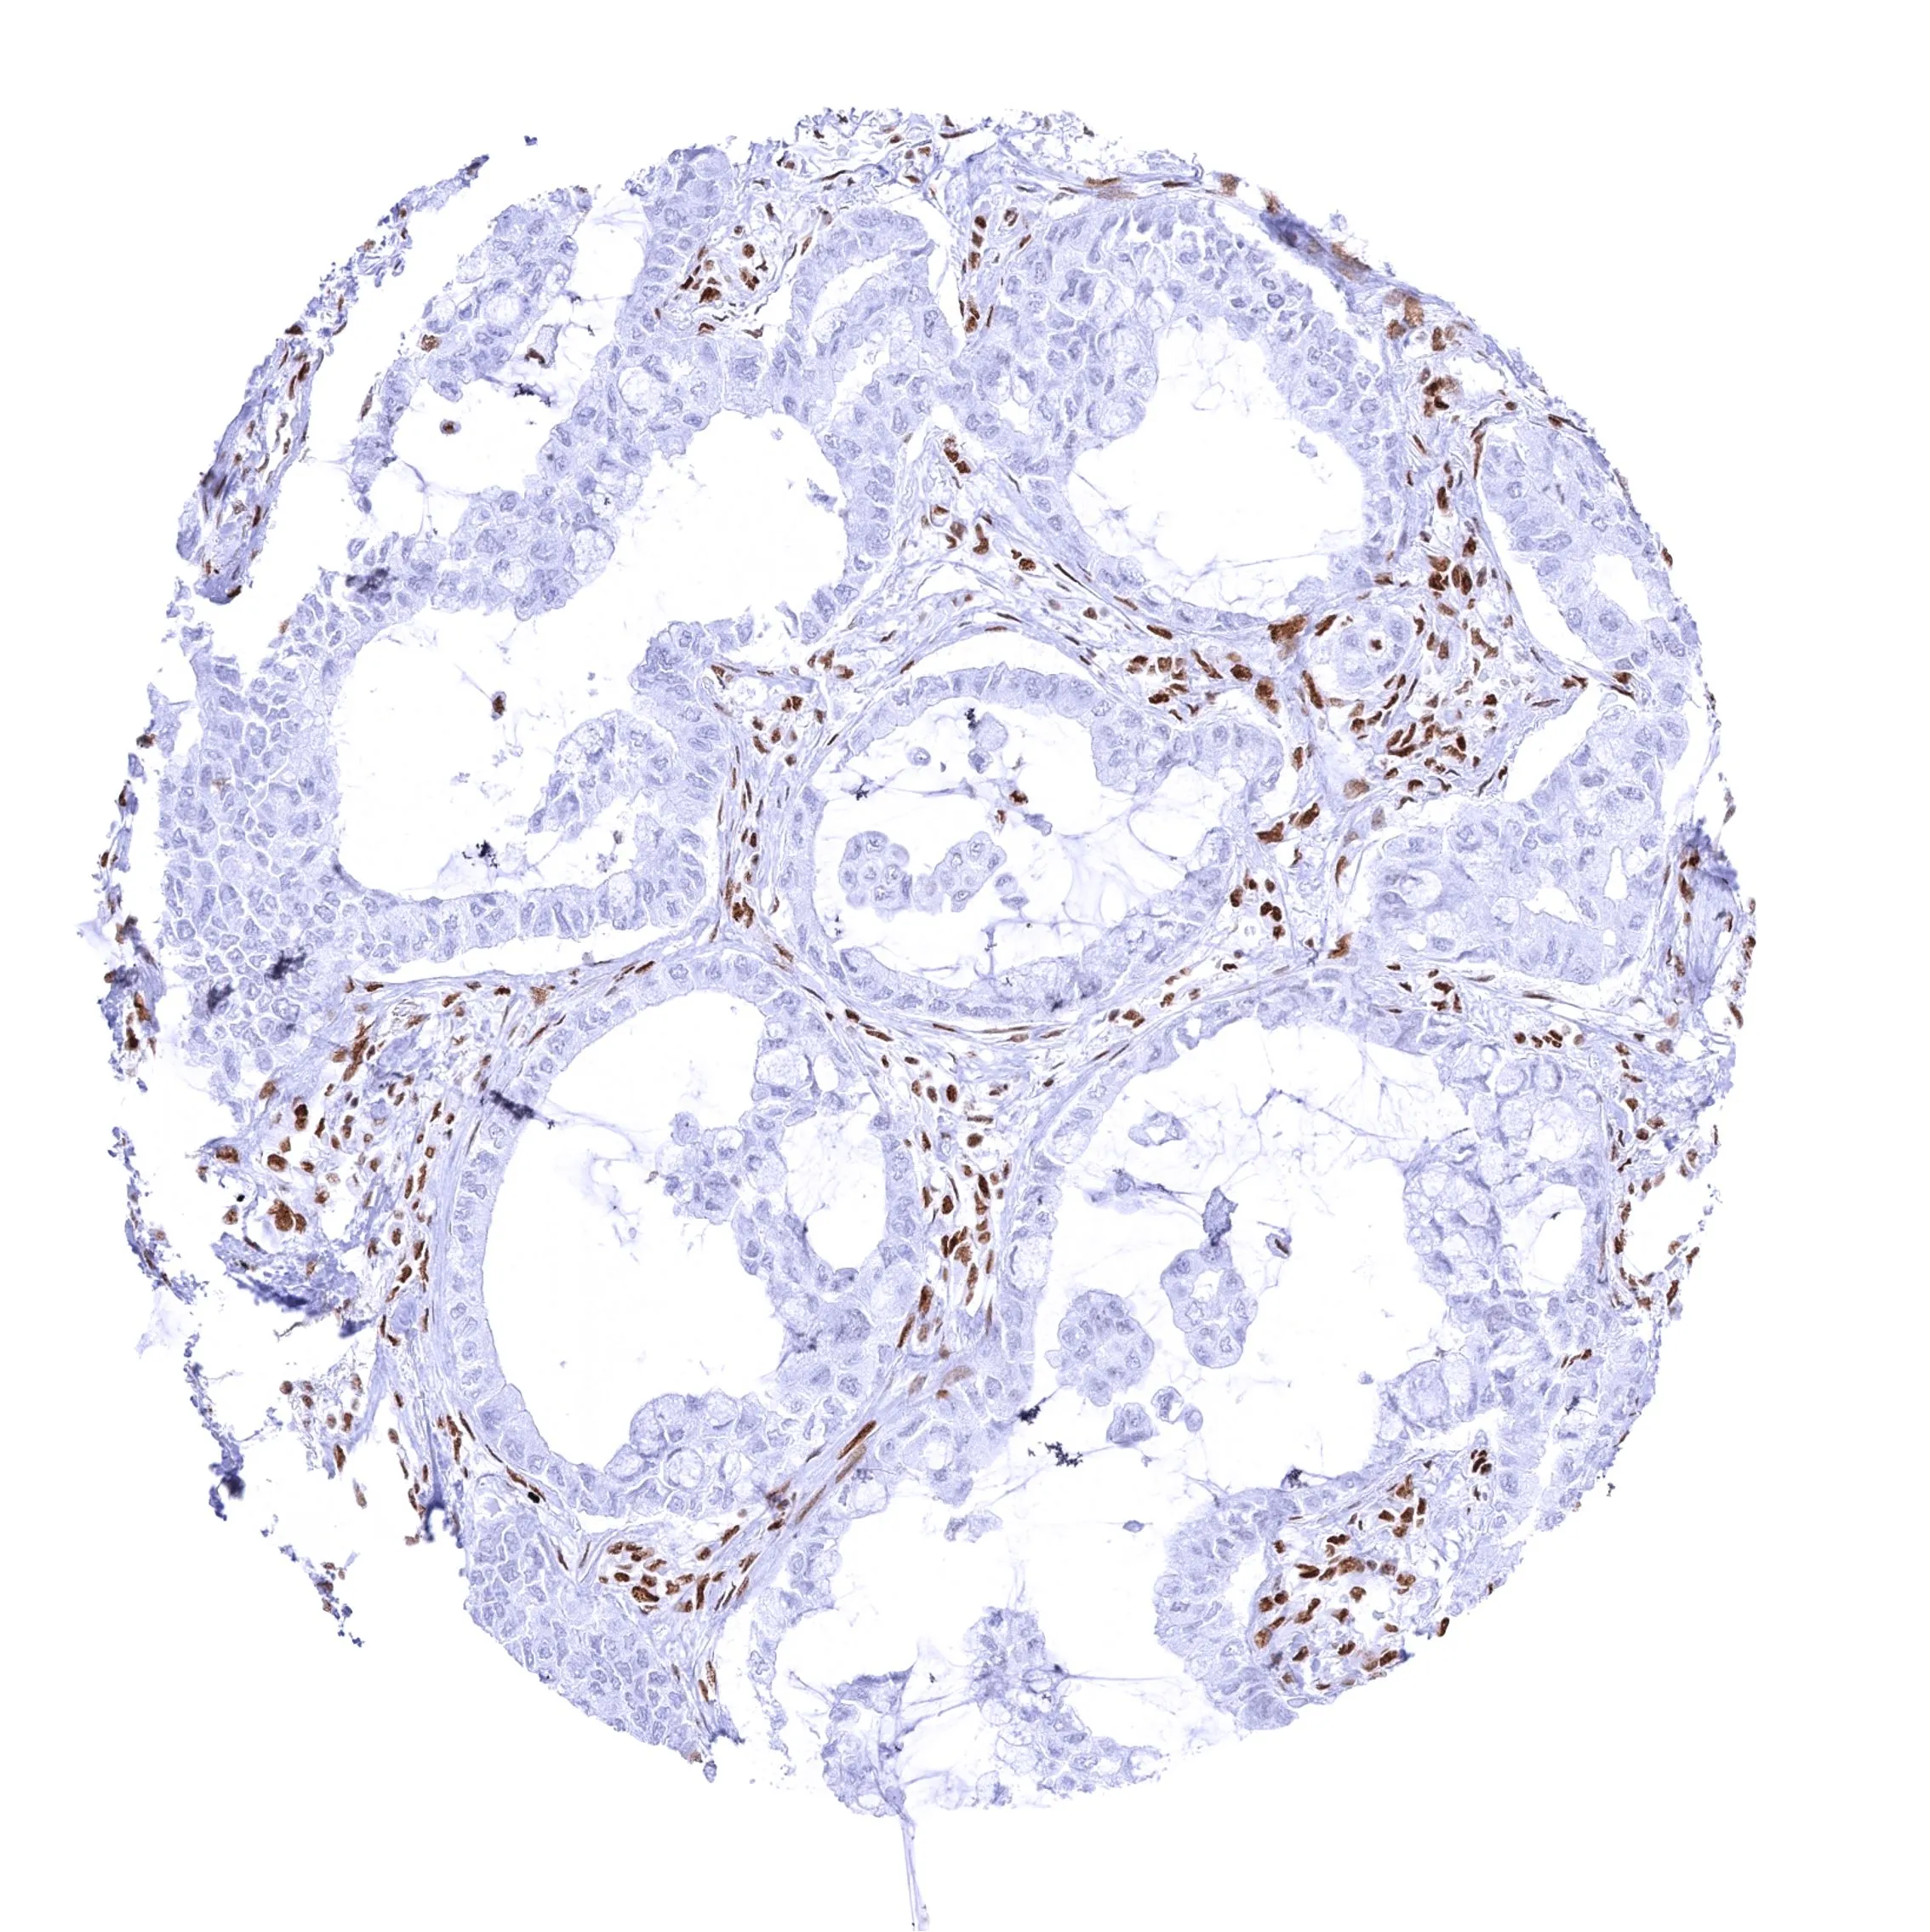

Anti-BRG1 antibody [MSVA-397R] HistoMAX™ used in IHC (Paraffin sections) (IHC-P). GTX04486

GTX04486 IHC-P Image

IHC-P analysis of human pancreatic ductal adenocarcinoma (PDAC) tissue using GTX04486 BRG1 antibody [MSVA-397R] HistoMAX™.

Ductal adenocarcinoma of the pancreas with complete loss of BRG1 staining in all tumor cells.